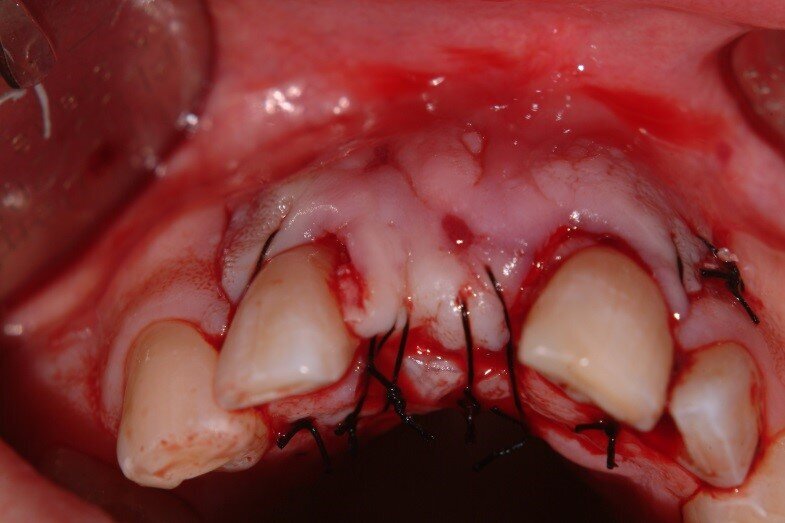

5. The flap was sutured with 4-0 silk to achieve primary closure over the site. (Fig. 11)